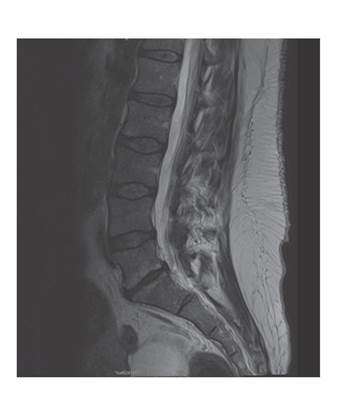

En RM pelviana de octubre del 2022 se apreció imagen ocupacional de aproximadamente 9,5 x 10 cm en hemipelvis derecha con alta intensidad de señal en secuencias potenciadas en T1 y T2 sugiriendo tumoración de estirpe grasa con efecto masa sobre estructuras intraabdominales, desplazando el recto, cuello uterino y vagina hacia el lado izquierdo (Figura 2 y Figura 3). En su porción lateral se introducía ampliamente por escotadura ciática derecha. Se procedió a la realización de punción aspiración con aguja fina, con abordaje posterior, bajo control de tomografía axial computarizada (PAAF-TAC) (Figura 4) de masa intrapélvica, obteniendo muestra para estudio histológico. El informe anatomopatológico confirmó tejido de aspecto adiposo maduro, compatible con lipoma por lo que se derivó a consulta de Cirugía.

Figura 3. Serie sagital de RM pelvis en T2. Imagen de masa intraabdominal que penetra agujero ciático.